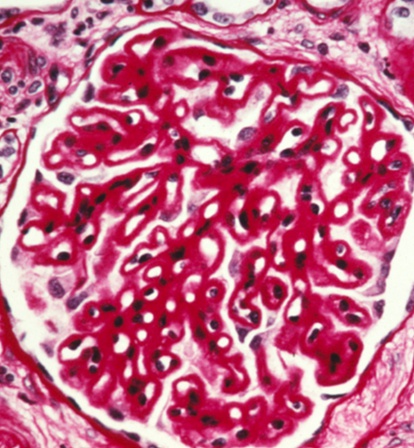

image: normal upright, abnormal lower left; pink deposition in abnormal

FSGS

more serious/dangerous version of MCD

IgM, C3